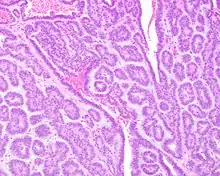

Canalicular adenoma growths are usually small at the time they are noticed, with an average size of about 1.6 cm.[1] Their histologic appearance is very distinct, with a channel-like pattern between cords and ribbons; the pattern has been described as resembling a "string of pearls."

The growths often contain are often small bight squamous balls, or morules. They also tyipcally contain a well-developed supporting tissue - a fibrous stroma - which is rich in hyaluronic acid and chondroitin sulphate.[1] In a few cases, the growths may contain small calcium deposits or microliths. Although it is seldom necessary, a pathologist can confirm the existence of canalicular adenoma through immunohistochemistry studies, with the cells reacting with pancytokeratin, S100 protein and SOX10, with a delicate GFAP reaction around the periphery.[5][1][6][7] Although it is a benign tumor, a positive diagnosis of canalicular adenoma may be necessary to exclude the existence of other medical conditions such as a basal cell adenoma, pleomorphic adenoma, adenoid cystic carcinoma, and polymorphous adenocarcinoma.